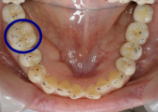

臼歯部において、第一大臼歯には7~8点の接触点が必要といわれています。しかし、保険適用の銀歯だと、咬む接触点は2~3点が限界です。それは、材料的に適合精度に限界があり、製作工程1回と少ないからです。これでは、噛めるとは言えません。見た目もよくありません。